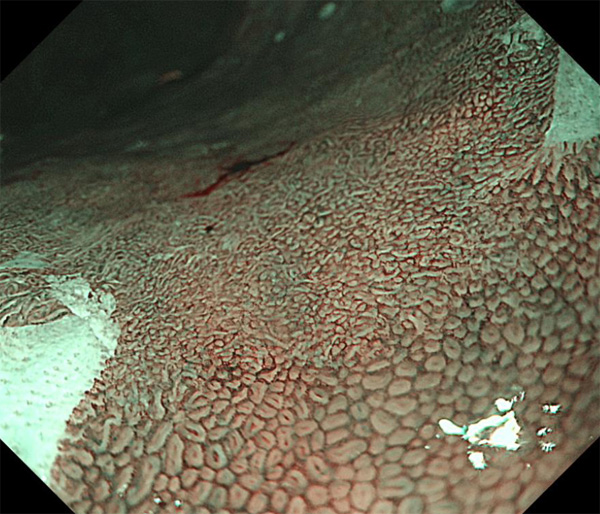

内視鏡所見と病理組織像の1対1対応が可能な症例を公募いたします。主にLSBEに発生した早期癌(HGDを含む)を対象としますが、興味深い症例であればSSBE癌でも結構です。採否は世話人へご一任ください。

症例呈示希望者は応募用紙に記入の上、代表的な内視鏡(2枚)、切除標本(新鮮、固定)、切り出し図、マッピング、代表的組織像とともに、Barrett 食道研究会事務局 barrett.shinshu@gmail.comへお申し込み下さい(10MB以下でお願い致します)。

特に、本邦では極めて稀なlong segment Barrett’s esophagus(LSBE)から発生した早期癌は、診断に難渋する場合も多く、欧米ではランダム生検による検出が標準的とされています。背景のBarrett食道もろとも全体を内視鏡切除+ラジオ波焼灼する欧米と異なり、ESDで内視鏡的な局所切除が基本の本邦では、存在診断+範囲診断(特に水平)を的確に行うことが不可欠です。

そのためには、一流の病理医による組織学的診断とエキスパート内視鏡医による拡大内視鏡像との一対一対応を徹底的に行うことで、『本来、見えないであろう拡大所見の先にある組織構築像が診えてくる』所まで内視鏡診断レベルを上げていく必要があります。その実現には、一対一対応を追究した症例(特にLSBE発生例)1例でも多く経験するしかありません。本研究会でBarrett食道腺癌(LSBE発生早期病変)を共に学び、拡大内視鏡像の一歩先を診るスキルを習得しましょう!一人でも多くの皆様のご参加をお待ちしています。